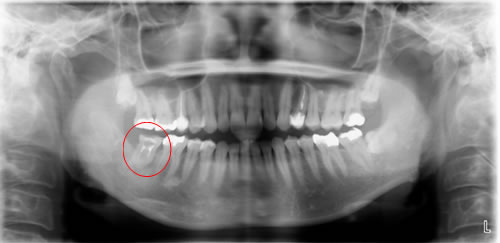

![]() |

|

移植後 |